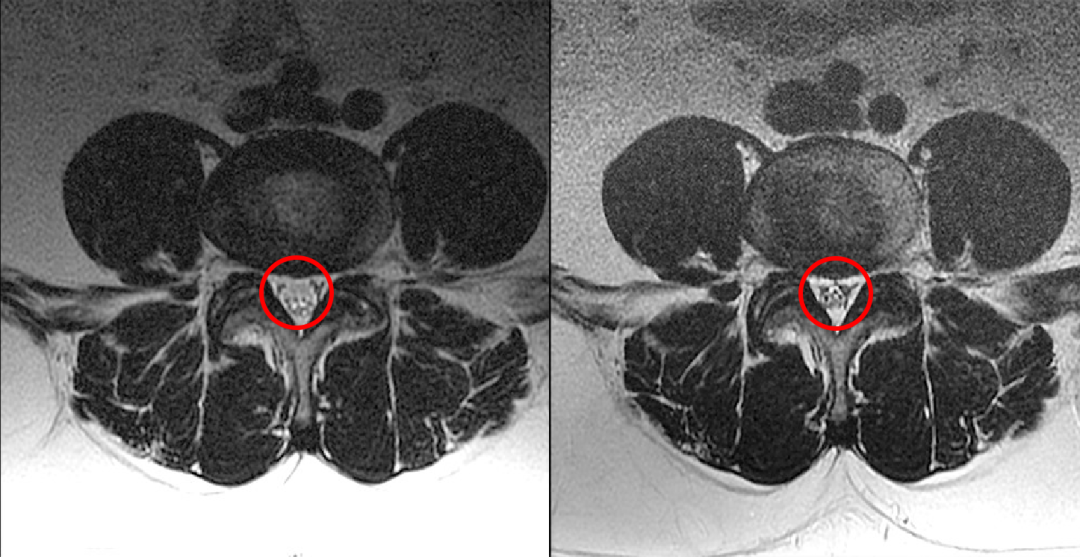

4.5 年前和现在的腰椎 MR T2WI 轴位对比:L4-L5 水平,现在的 MR 发现马尾神经位置前移,更加聚拢;而 4.5 年前的 MR 发现马尾神经位置靠后,分散。

回过头再看第一个病例,发现椎管内硬膜外脂肪增多,向前推挤马尾神经,使其相对聚拢

回过头再看第二个病例,发现椎管内背侧硬膜外脂肪增多,超过椎板前缘,向前推挤马尾神经,使其明显聚拢

轴面上 T2WI 收到硬膜外脂肪的推挤,硬膜囊可以发生变形(正常为椭圆形)通常为多边形(A)、星状(B)或 Y 形或 V 形(C-D)

同样的,回头看第一个病例也会发现硬脊膜椎韧带,是由于硬膜外脂肪增多而把他显示出来